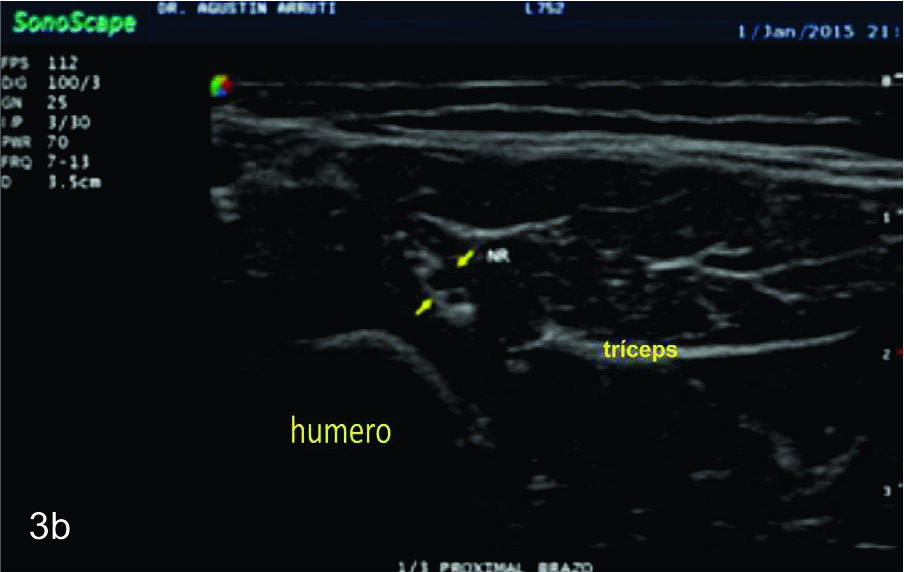

Figura 3

Nervio radial

Serie de cortes axiales del nervio radial desde su origen a nivel del hueco axilar hasta su bifurcación en sus dos ramas terminales a nivel del codo. Se identifica el mismo señalado por flechas amarillas y con las letras NR. AH-arteria humeral, tríceps- músculo tríceps, BA- músculo braquial anterior, CB- músculo coraco braquial, BR- músculo braquiorradial. A- axila, B- tercio proximal del brazo, C- tercio medio del brazo, D- tercio distal del brazo, E- codo, las flechas señalan las dos ramas terminales del nervio radial.